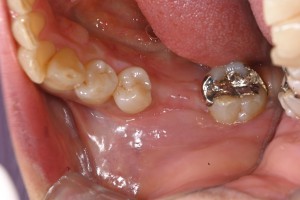

以下、実際の症例です

サイナスリフト・クレスタルアプローチ

インプラント前

インプラント後

サイナスリフト・ラテラルアプローチ